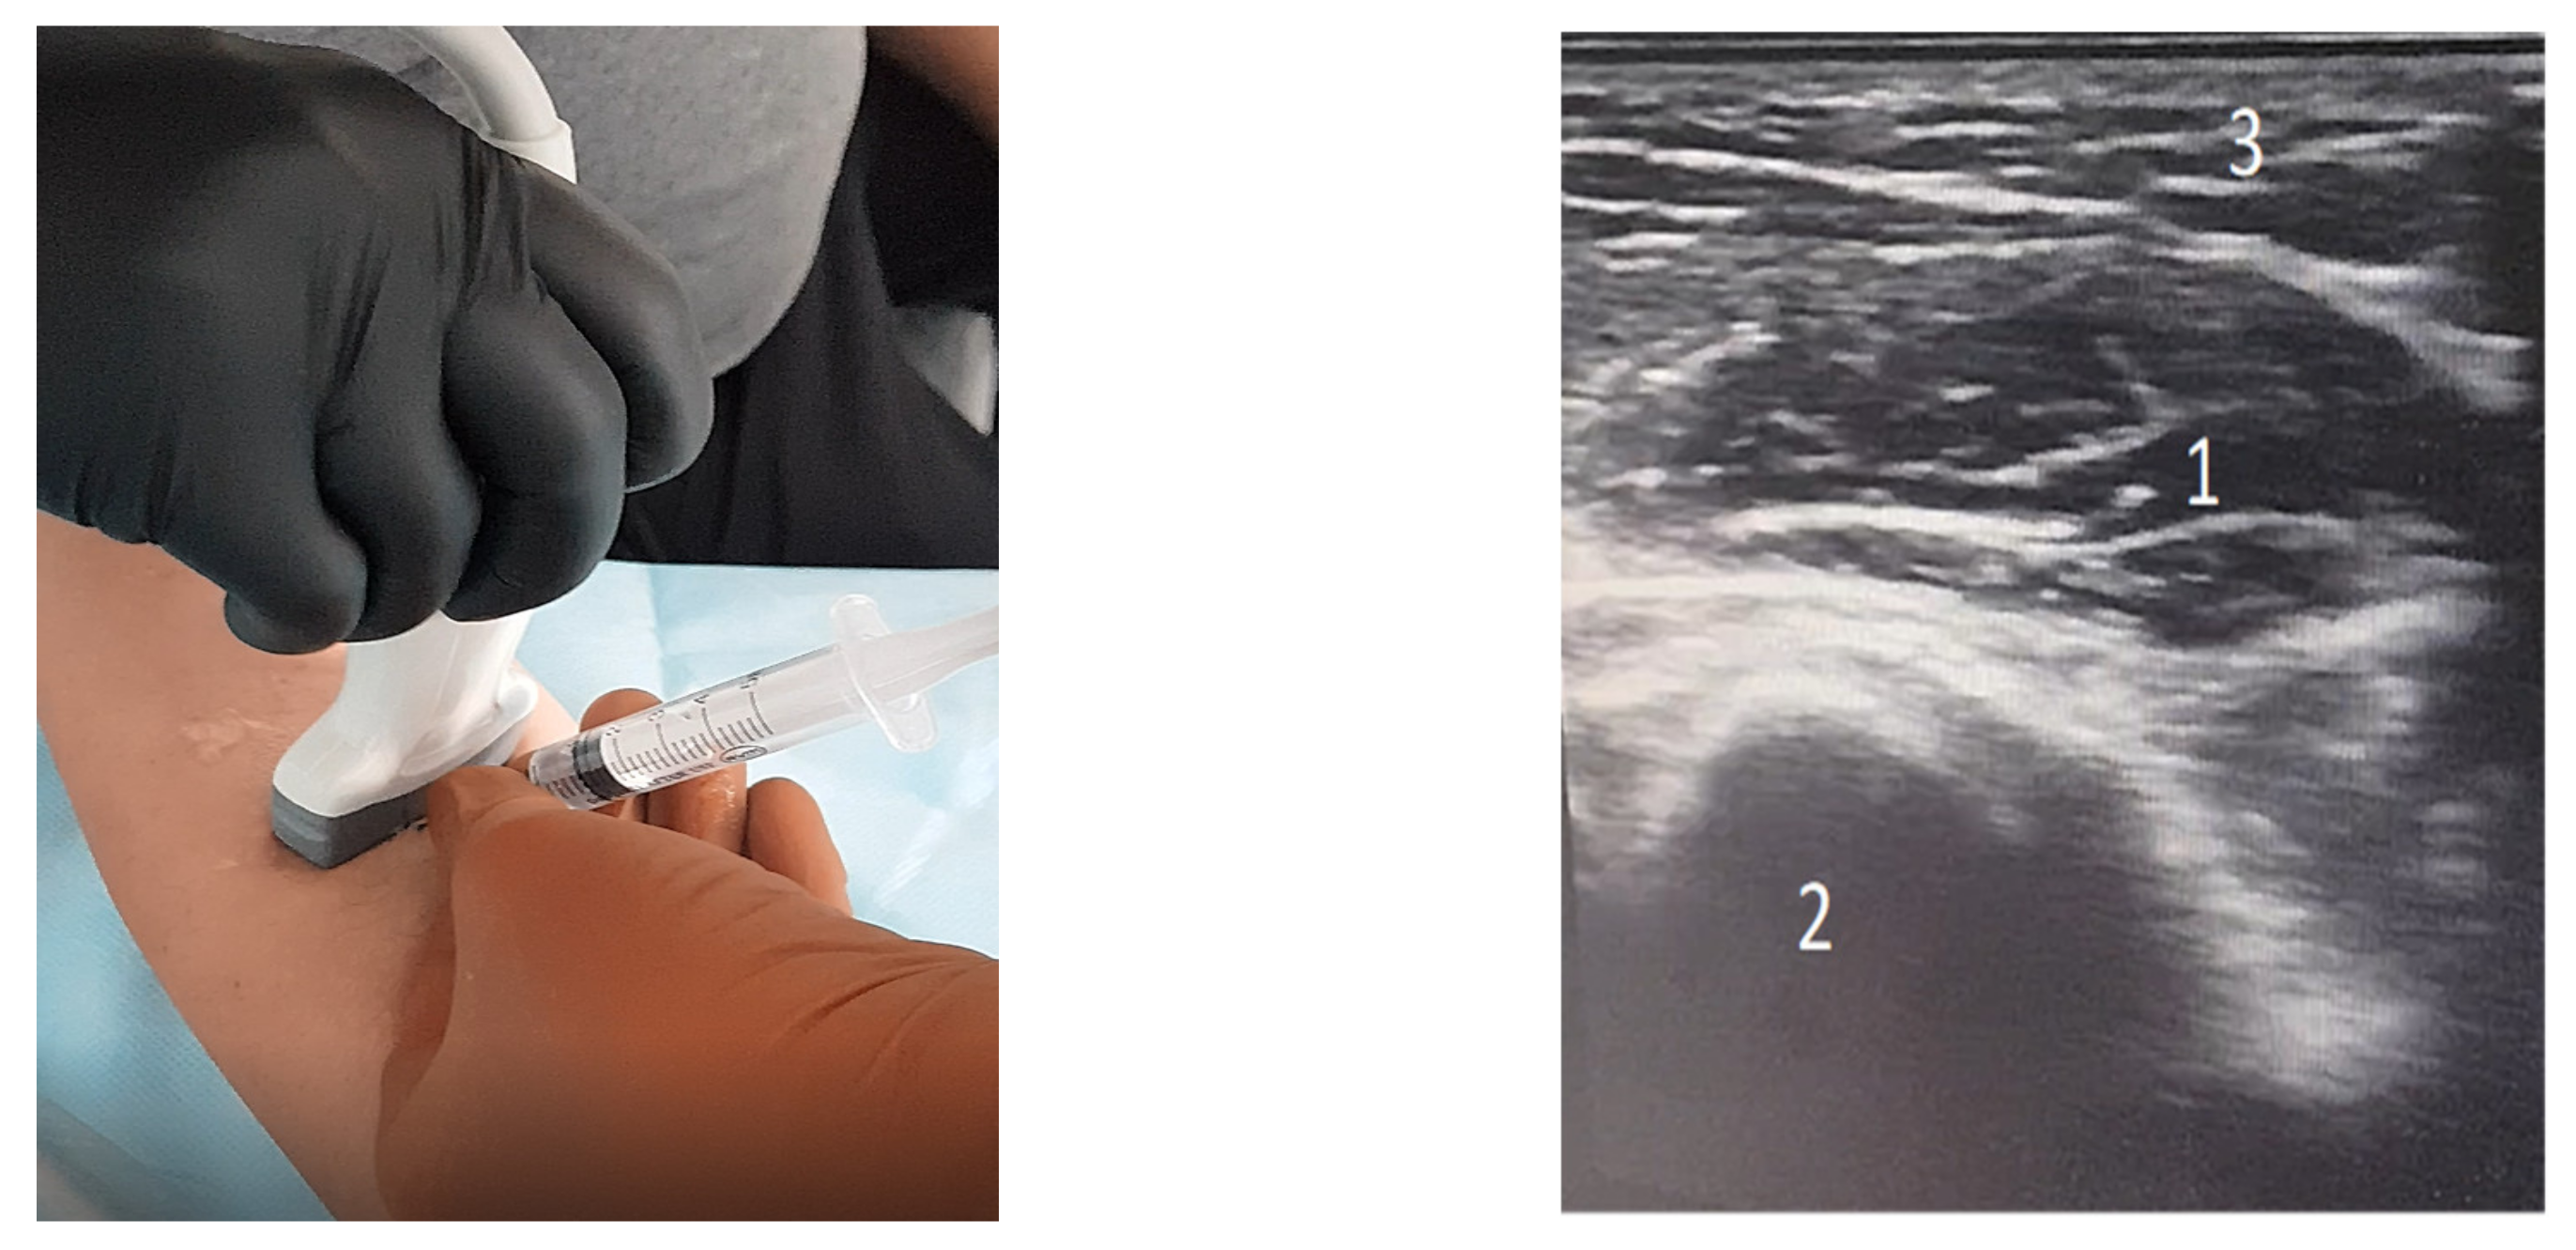

1. Introduction

2. Materials and Methods

2.5. Statistical Analysis